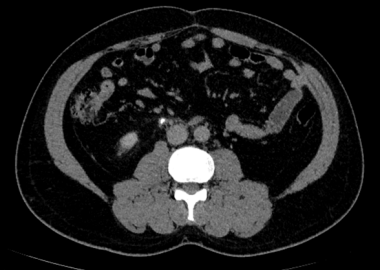

Chẩn đoán hình ảnh mô mềm tiên tiến cho vùng bụng.

Tăng cường độ tương phản I-ốt.

Hỗ trợ đánh giá an toàn cho bệnh nhân.

Đảm bảo hình ảnh chất lượng cao.